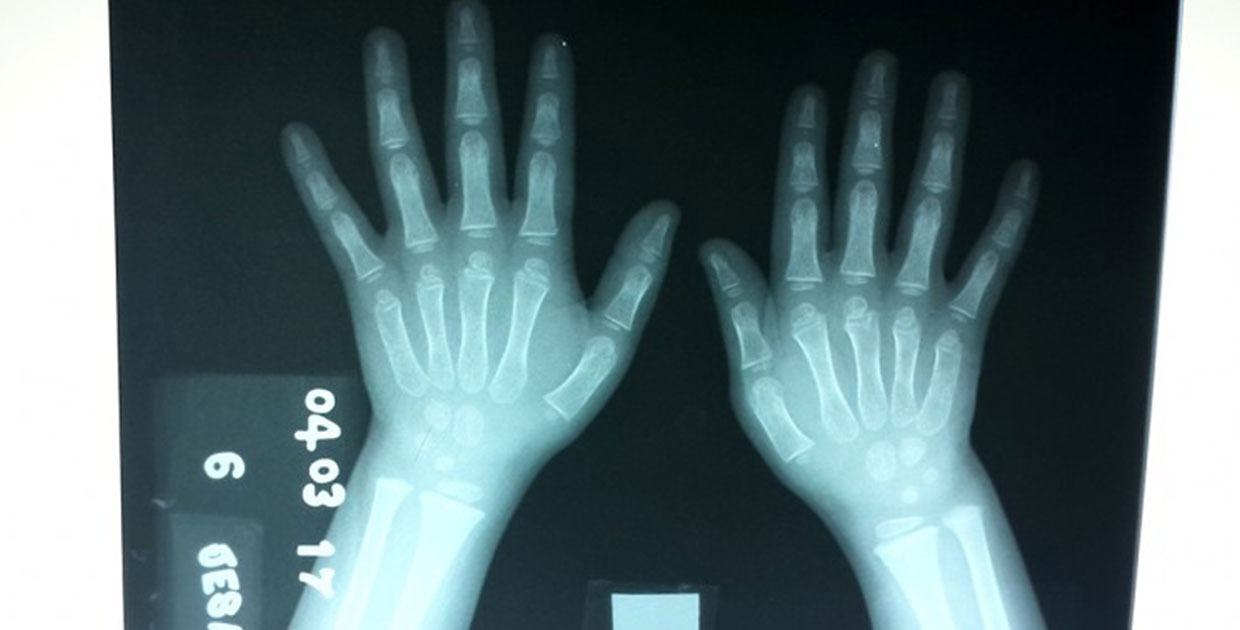

Los especialistas del Grupo Parma  (PAttern Recognition and MAchine Learning Group), demostraron que la utilización de filtros previos para tratar imágenes mejora en un 42% la efectividad con la que las computadoras pueden determinar la edad de los niños a través de radiografías de su mano izquierda.

Al notar diferencias entre la edad ósea y la edad real de los infantes, los médicos pueden detectar alguna enfermedad de crecimiento en la persona. Foto: Cortesía S. Calderón.

Que un software pueda tomar una imagen de rayos X y pueda decir cuál es la edad estimada de un niño, en meses, es muy relevante en medicina; porque si un técnico recibe a un niño, le saca una imagen de rayos X y resulta que el software dice 30 meses, y el niño tiene más o menos edad, entonces eso le ayuda a diagnosticar algún problema de crecimiento.